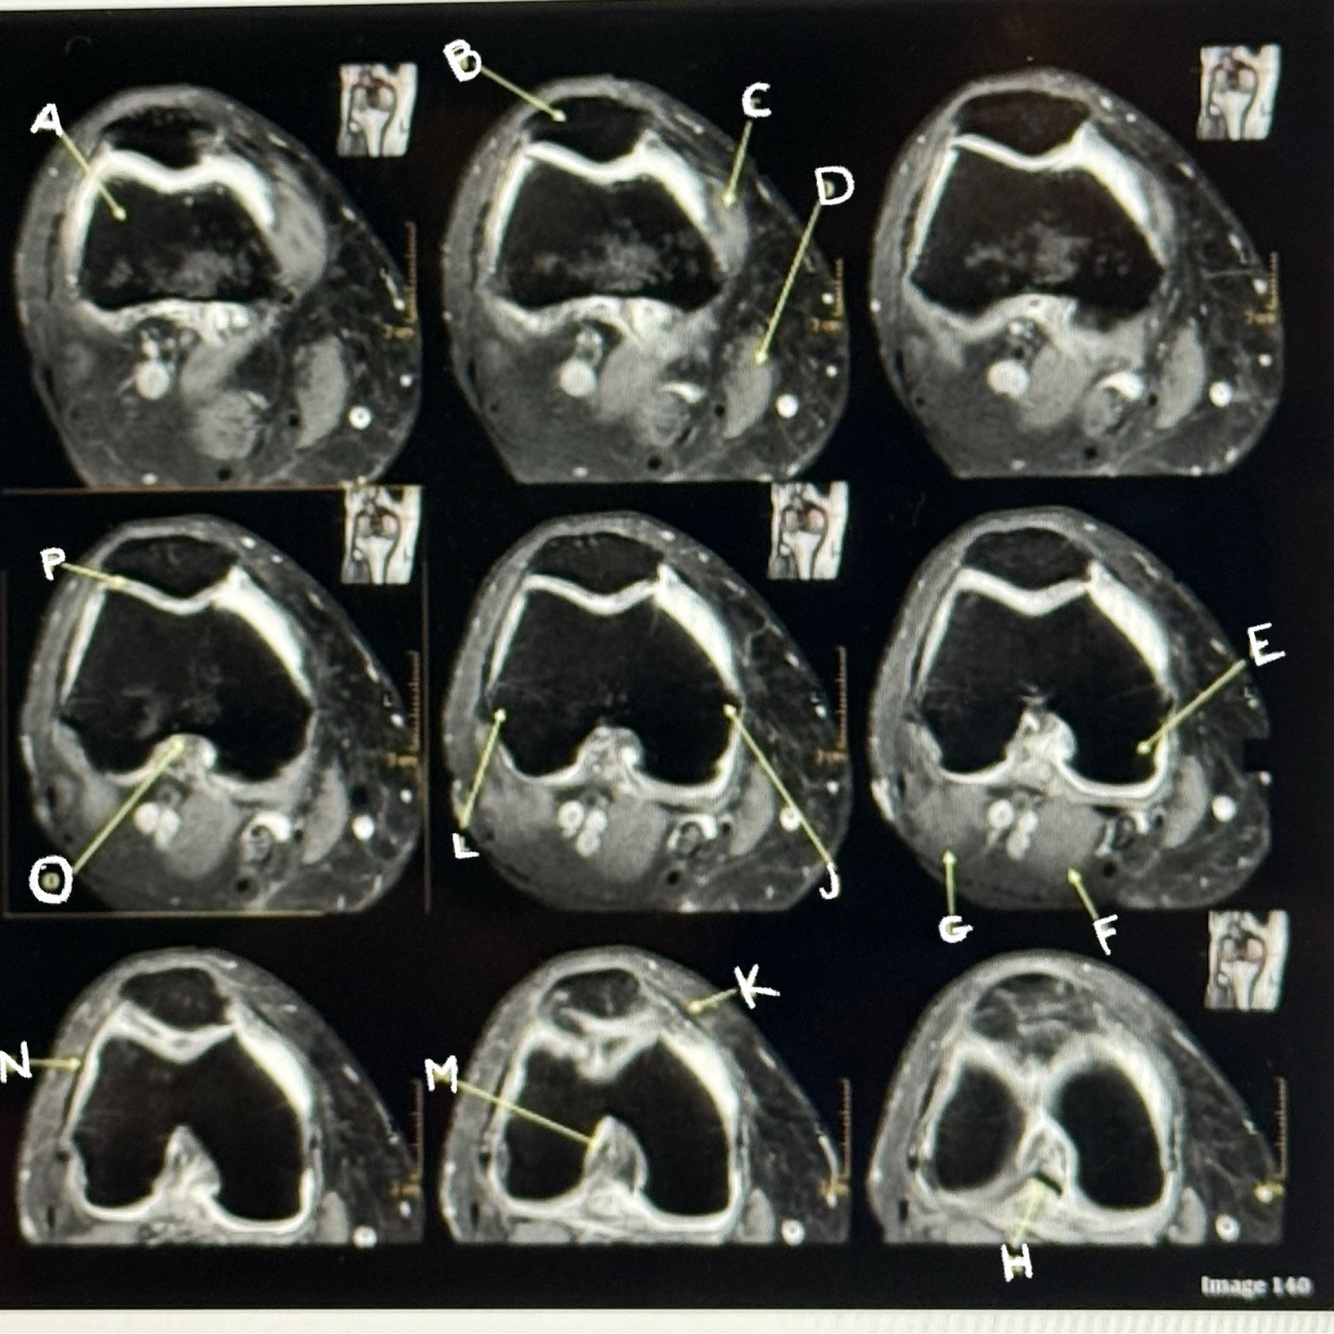

Letter P points to the

Articular cartilage

39

Letter M points to the

Anterior cruciate ligament

40

Letter N points to the

Lateral retinaculum

41

Letter O points to the

Intercondylar fossa

42

Letter K points to the

Medial retinaculum

43

Letter L points to the

Lateral epicondyle

44

Letter H points to the

Posterior cruciate ligament (PCL)